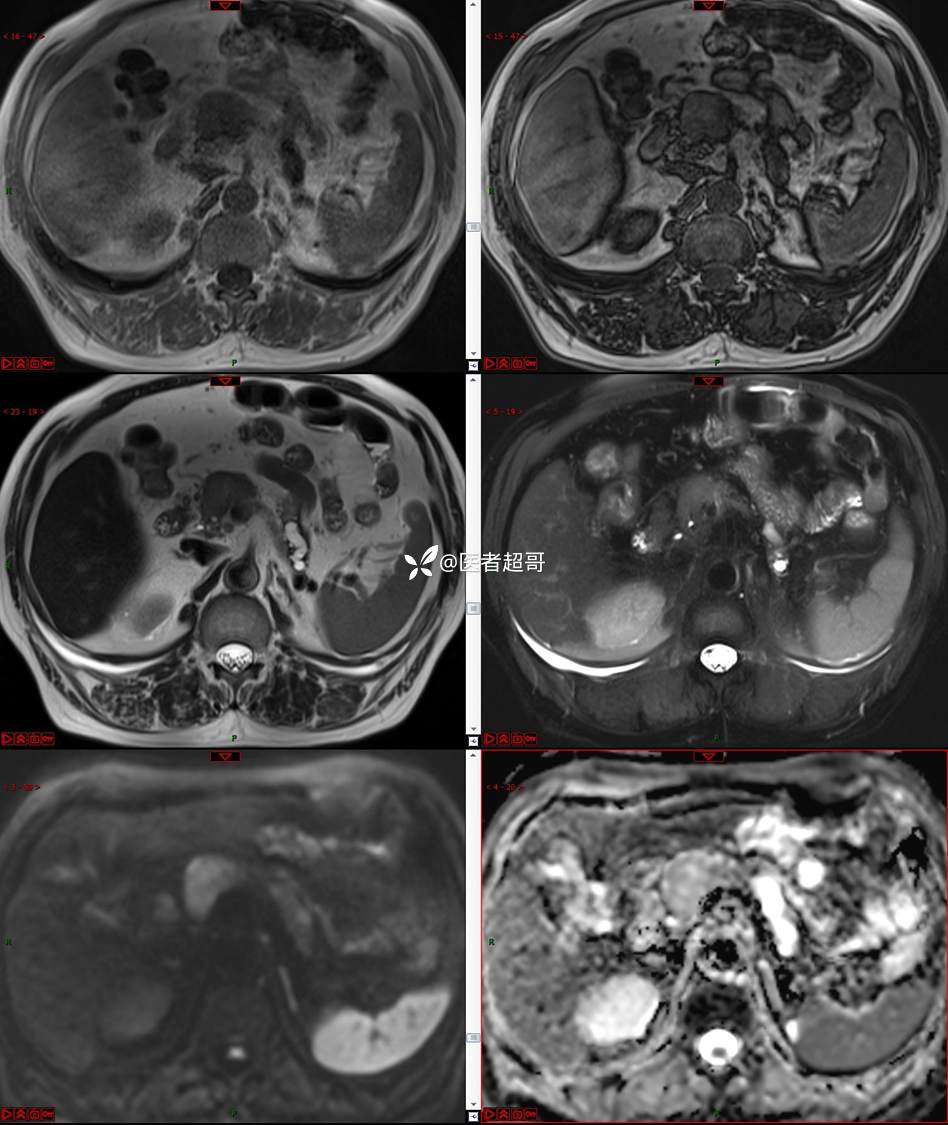

【影诊笔记677】查体发现胰腺占位性病变1周,细节决定成败,请诊断分析!

主 诉:查体发现胰腺占位性病变1周。

现病史:患者1周前在当地查体时发现胰腺占位性病变,无恶心、呕吐,无腹痛,无寒战、高热,无咳嗽、咳痰等异常不适,来我院门诊查上腹部CT平扫+强化:胰腺尾部异常密度灶。今为求进一步治疗,门诊以“胰腺占位性病变”收入院。患者自发病以来,一般情况可,神志清,精神可,普通饮食,二便正常,体重及体力无明显改变。

既往史:既往糖尿病病史2年,口服二甲双胍早晚各一片和格列吡嗪早晚各一片,否认高血压、心脑血管病等疾病史,否认肝炎、结核或其他传染病史及密切接触史,预防接种史不详,否认药物及食物过敏史,否认外伤史,12年前肾癌切除术手术史,否认输血史,其它无特殊。